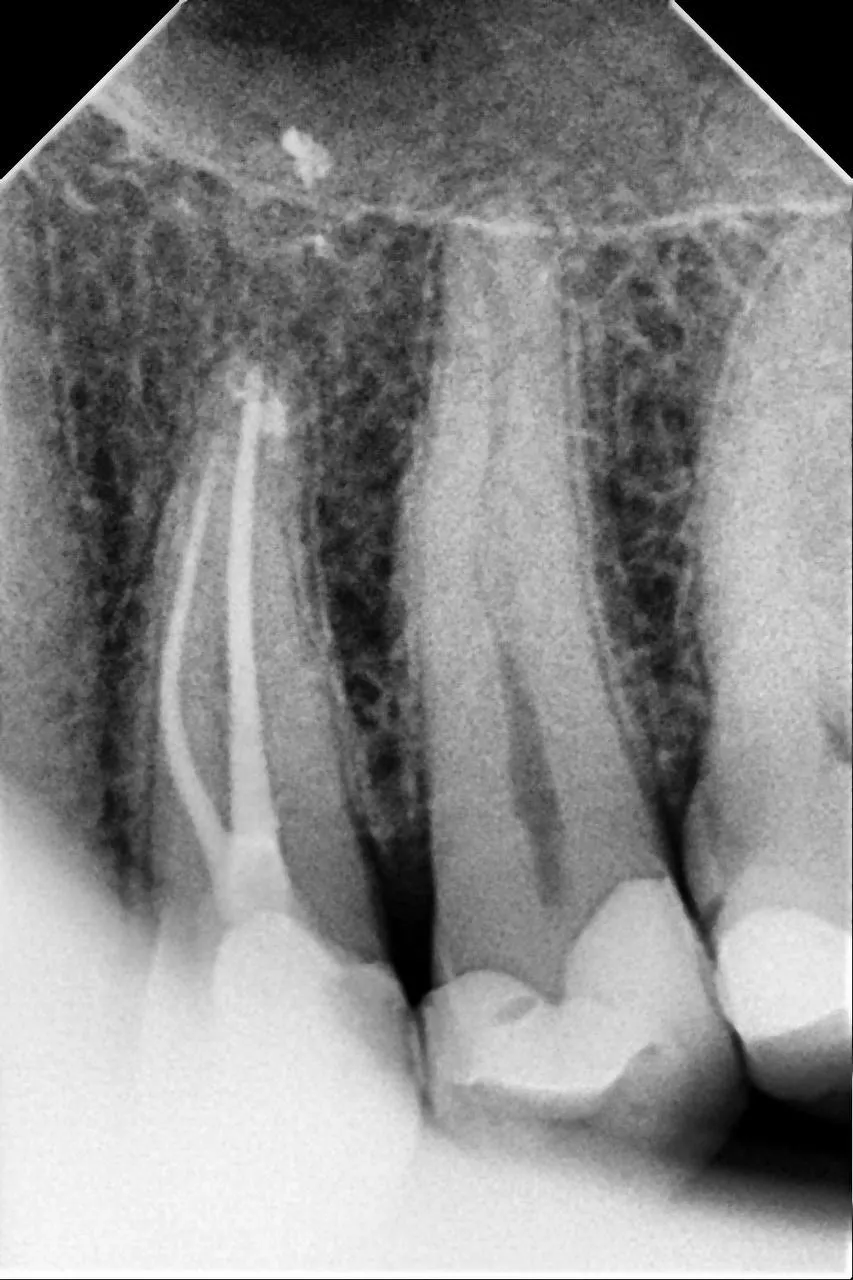

Вторинне ендо 14 зуба. Пропущений дистальний щічний канал